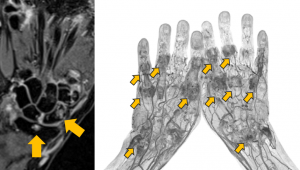

関節リウマチでは関節炎の結果起こってしまう 関節破壊(骨が溶ける骨びらん)や変形の原因となる関節の脱臼などが無いか確認するために行います。合併症や副作用の有無を確認するための肺のレントゲン検査と合わせて、調子が良くても年に1回は手足や関節痛がある部位のレントゲン検査は受けるようにしましょう。

画像:レントゲン検査で確認される小さな骨びらん

レントゲン検査で

確認される小さな骨びらん